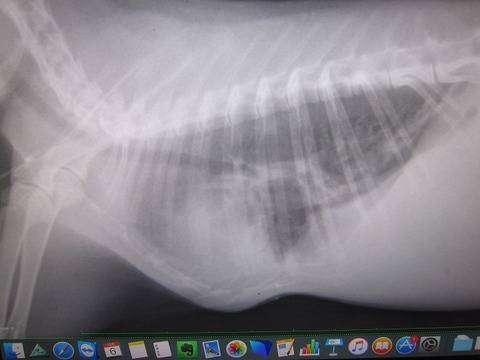

3月26日(金)病院 1.30kg

折り返して減ってきてる予想だったのに増えてて…

朝の掃除で糞が少なく感じたから、出る方が悪かったからとか???

この日は切歯の処置も。骨の歪みから伸びる方向も最初に比べると前へ、という感じ。

そして左側はもう処置をせんでも確定、かな。

排膿の処置、前後の違いはわかりづらいか…。

膿だけでなく空気(気泡)も出てくると。

繋がってるであろう口から空気が入ったか、

膿自体から発生するガスか、ここらで抗生剤の種類を変えることに。